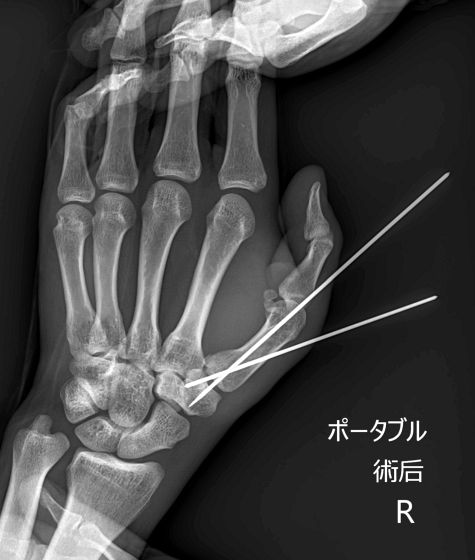

午後4時頃まで待って手術開始。ワイヤーを挿入した際のレントゲン写真はこんな感じ。

ワイヤーは皮膚から少し飛び出す長さで切断し、ワイヤーが飛び出た上からシーネ(当て木)を当てた状態で包帯を巻かれました。